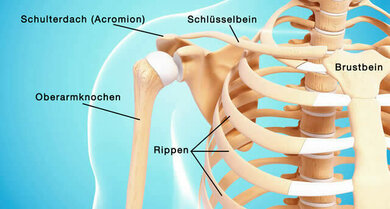

In der Skizze: Die Lage des Schlüsselbeins